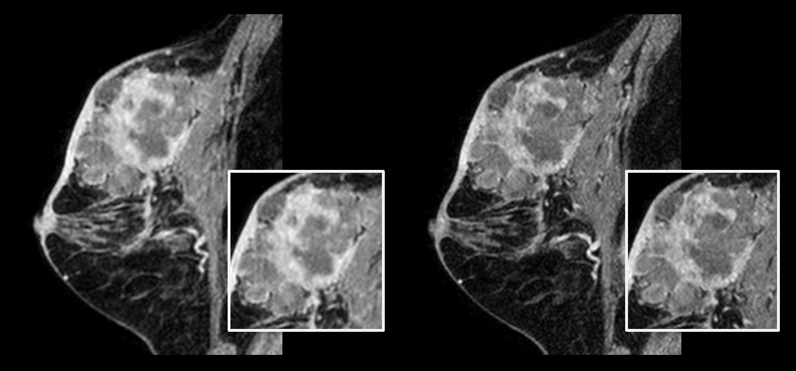

Bei herkömmlichen MR-Scanmethoden bedeutet die Bildgebung mit hoher Auflösung mitunter eine lange Scandauer. Dies kann für Patienten mit Schmerzen oder Engegefühlen sehr schwierig sein. Auch für eine stark ausgelastete Abteilung ist eine lange Scandauer für hochauflösende Bilder möglicherweise nicht in den Zeitplan integrierbar. Compressed SENSE ermöglicht schnelle isotrope 3D-Bilder im Submillimeterbereich (0,7 mm oder weniger) in weniger als 5 Minuten, sodass auch herausfordernde Patientenfragestellungen und anatomische Strukturen zuverlässiger diagnostiziert werden können.

Links: Herkömmlicher 3D-mDIXON-XD-Scan mit isotroper Voxelgröße von 1,0 mm, Scandauer 2:22 Minuten Rechts: Compressed SENSE 3D-mDIXON-XD-Scan mit isotroper Voxelgröße von 0,8 mm, Scandauer 2:21 Minuten

Mit freundlicher Genehmigung von: Kurashiki Zentralkrankenhaus, Okayama. Japan

Bei Brustuntersuchungen ist eine hohe Auflösung wichtig, um sehr kleine Brustläsionen zu erkennen. Wir benötigen also T1- und T2-gewichtete 2D-Bilder in hoher räumlicher Auflösung, aber auch eine kurze Scandauer. Mit Compressed SENSE konnten wir die räumliche Auflösung und damit auch unsere Diagnosesicherheit erhöhen.“

Dr. Takashi Koyama, MD, PhD, diagnostischer Radiologe und Leiter des Radiologiezentrums und der diagnostischen Radiologie, Kurashiki Zentralkrankenhaus, Japan